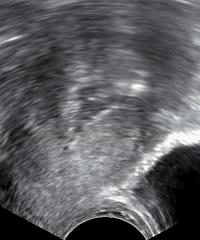

In postmenopausal bleeding, guidelines from the United States consider transvaginal ultrasonography to be an appropriate first-line procedure to identify which women are at higher risk of endometrial cancer. A cut-off threshold of 3 mm or less of endometrial thickness should be used for in women with postmenopausal bleeding in the following cases:

- Not having used hormone replacement therapy for a year or more

- Usage of continuous hormone replacement therapy consisting of both an estrogen and a progestogen

A cut-off threshold of 5 mm or less should be used for women on sequential hormone replacement therapy consisting both of an estrogen and a progestogen.

It the endometrial thickness equals the cut-off threshold or is thinner, and the ultrasonography is otherwise reassuring, no further action need be taken. Further investigations should be carried out if symptoms recur.

If the ultrasonography is not reassuring, hysteroscopy and endometrial biopsy should be performed. The biopsy may be obtained either by curettage at the same time as inpatient or outpatient hysteroscopy, or by using an endometrium sampling device such as a pipelle which can practically be done directly after the ultrasonography.